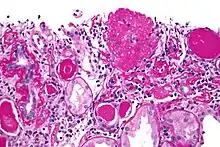

![]() | |

| Light micrograph of focal segmental glomerulosclerosis, hilar variant. Kidney biopsy. PAS stain. | |